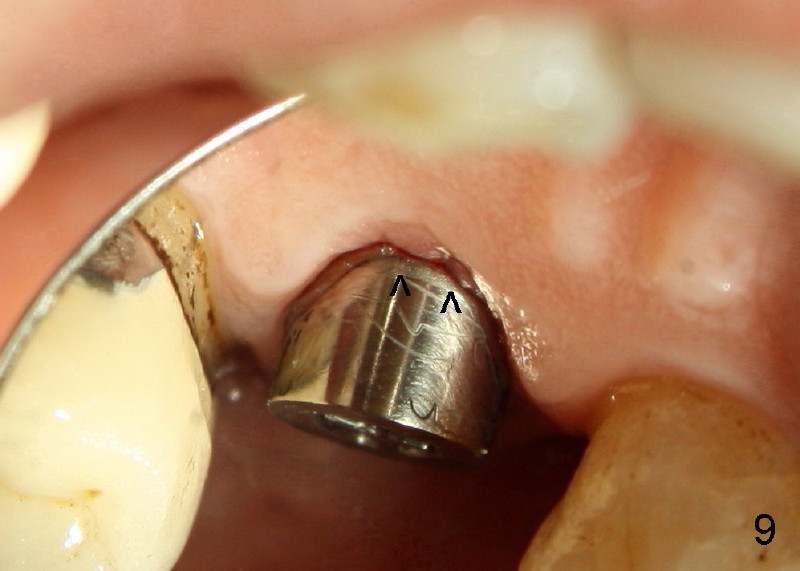

Fig.7-9 are taken 3.5 months postop.  Buccal gingiva appears to have elevated (Fig.8 arrow, as compared to Fig.5 B).  The rough surface seems to have been partially covered by lingual gingiva (Fig.9 arrowheads, as compared to Fig.6).